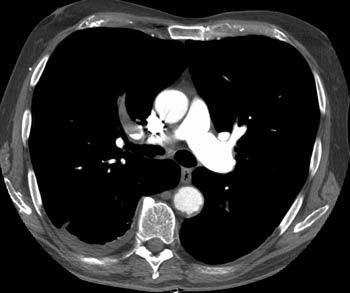

Clot completely occludes the right upper lobe pulmonary artery